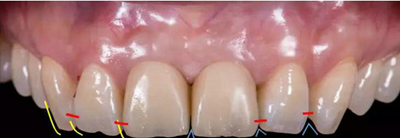

種植過渡義齒試戴,調(diào)整唇側(cè)凸度,切端位置

患者剛戴入過渡義齒時(shí),發(fā)現(xiàn)牙齦泛白,范圍不超過鄰牙終點(diǎn)。若患者休息10分鐘后,牙齦顏色恢復(fù)正常,則說明穿齦輪廓設(shè)計(jì)合理。

種植過渡義齒戴牙后1個(gè)月,患者希望改善義齒美觀度,并進(jìn)一步減少唇側(cè)凸度

患者試戴1個(gè)月后,發(fā)現(xiàn)牙齦塑性效果良好,過渡義齒穿齦部分不需要修改

種植過渡義齒戴牙后3個(gè)月,牙齦形態(tài)穩(wěn)定

過渡義齒制作完成及試戴

過渡義齒佩戴3個(gè)月后